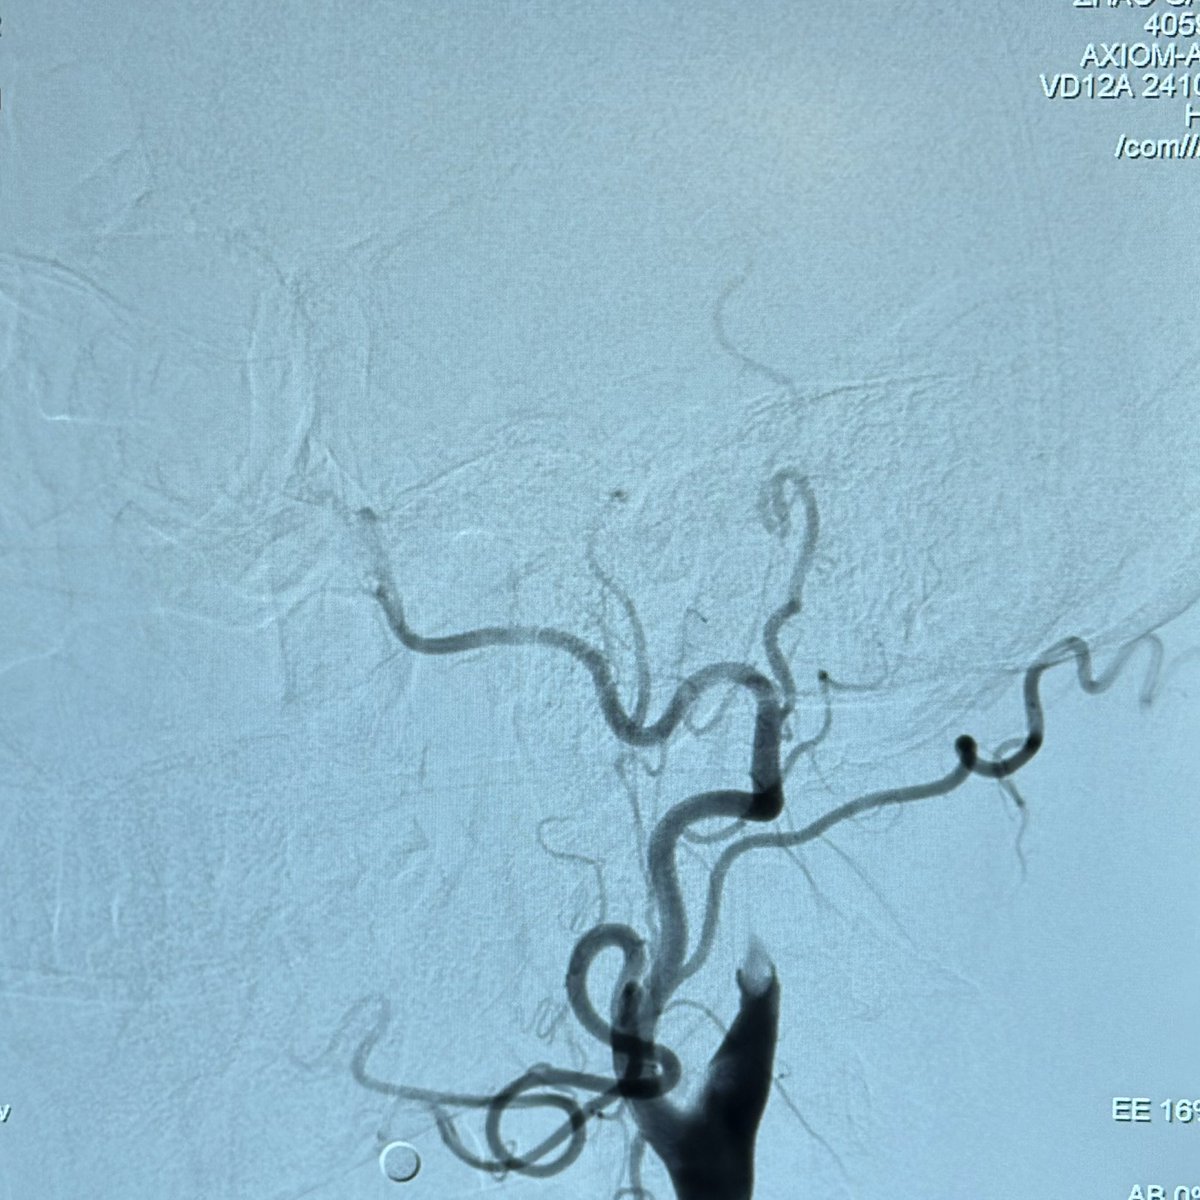

This 🧔♂️ presents with a subarachnoid haemorrhage in the left suprasellar cistern

DSA shows an infundibulum/ aneurysm of the left PCom. To coil or not was a conundrum. Every expert has a different take

The size is 3.4 mm x 2.6 and it is located in the region of the bleed.

What would you do?